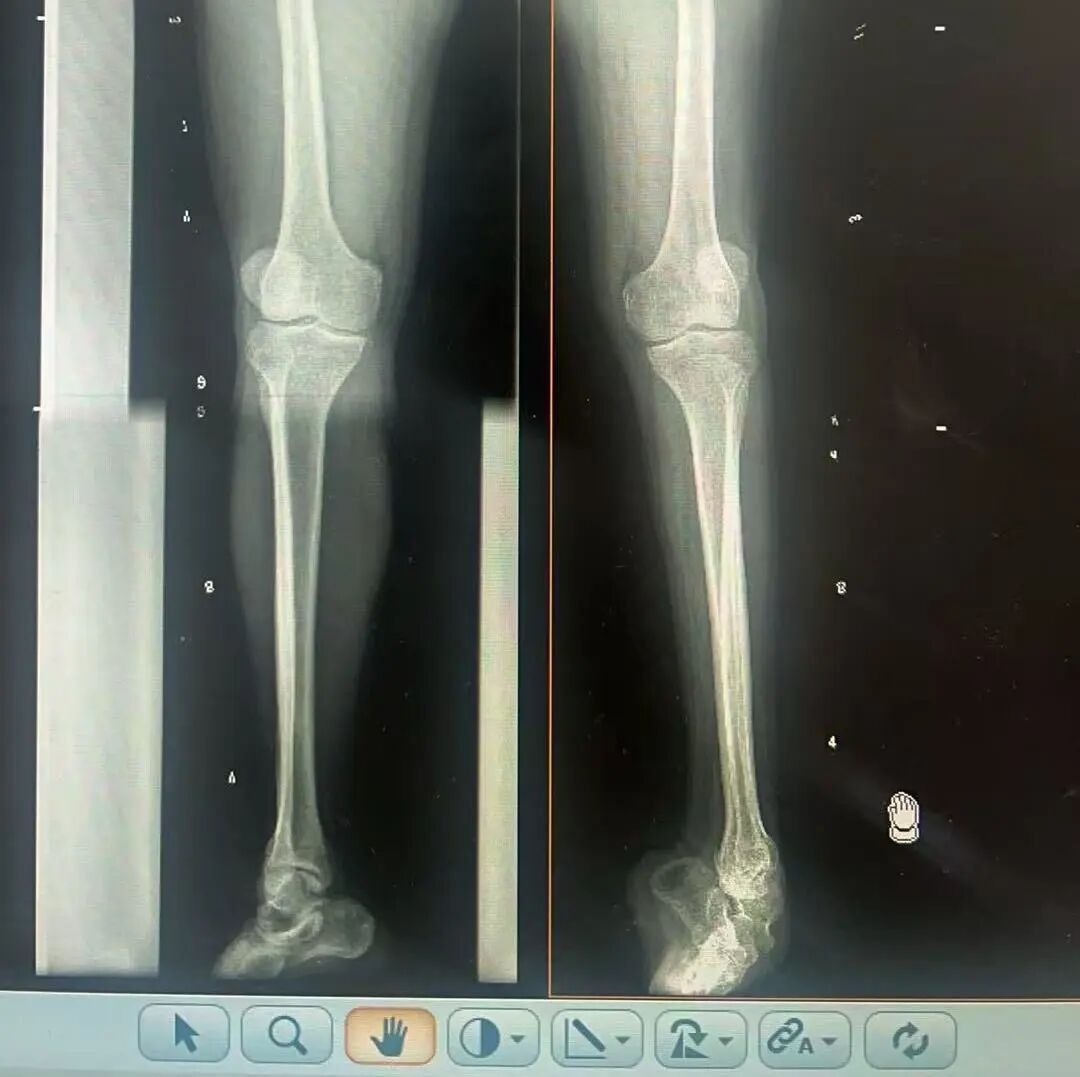

術(shù)前X光片 VS 術(shù)后治療效果

三十八年前,一紙“脊髓灰質(zhì)炎”的診斷,讓陽先生的人生染上了陰霾。闖過了急性期的鬼門關(guān),但后遺癥——嚴重的左踝馬蹄內(nèi)翻足畸形,是一道無形的枷鎖,禁錮著他的成長與自由。骨盆傾斜、雙腿不等長、左腳嚴重內(nèi)翻,他成長成人中行走的每一步,都伴隨著難以言說的艱辛。

骨科隨即為陽先生進行了全面的檢查。診斷明確而復(fù)雜:陽先生患有脊髓灰質(zhì)炎后遺癥、左踝馬蹄內(nèi)翻足、骨盆傾斜……面對這張沉甸甸的診斷書,由肢體功能重建顯微修復(fù)學(xué)科組長鄭群龍所帶領(lǐng)的醫(yī)療團隊沒有畏懼,“這是一個家庭38年的堅守與期盼,我們必須全力以赴”

針對陽先生的復(fù)雜情況,鄭群龍醫(yī)師團隊制定了詳盡的手術(shù)方案:左踝關(guān)節(jié)融合+馬蹄足畸形矯正+跟腱延長+外固定架固定術(shù)。手術(shù)的核心,正是伊里扎洛夫技術(shù)。這項技術(shù)如同精密的“時空建筑學(xué)”,通過微創(chuàng)安裝環(huán)形外固定架,前足-后足安裝鋼環(huán),再將足的鋼環(huán)與脛骨的固定鋼環(huán)在踝關(guān)節(jié)前、后、左、右用帶關(guān)節(jié)的螺紋桿連接,由此構(gòu)建成一個能體外牽拉調(diào)控的三維立體構(gòu)型,在術(shù)后進行精準、緩慢的調(diào)整,一寸一寸逐步將畸形的骨骼、軟組織恢復(fù)到正常位置。

9月1日,在全麻狀態(tài)下,陽先生接受了伊里扎洛夫外固定架安裝術(shù)。鄭群龍團隊在陽先生左足足踝部植入克氏針及半針,安裝外固定架,通過支架的機械結(jié)構(gòu)對馬蹄內(nèi)翻畸形進行緩慢、持續(xù)的牽拉矯正。術(shù)后,鄭群龍團隊反復(fù)指導(dǎo)訓(xùn)練陽先生父子進行外固定架的日常調(diào)試,按照預(yù)定計劃每日調(diào)整螺桿,逐漸糾正足部畸形,并配合專業(yè)的康復(fù)訓(xùn)練,包括踝關(guān)節(jié)主動及被動活動、下肢肌力訓(xùn)練等項目促進陽先生腿部肢體功能恢復(fù),預(yù)防肌肉萎縮及關(guān)節(jié)僵硬。